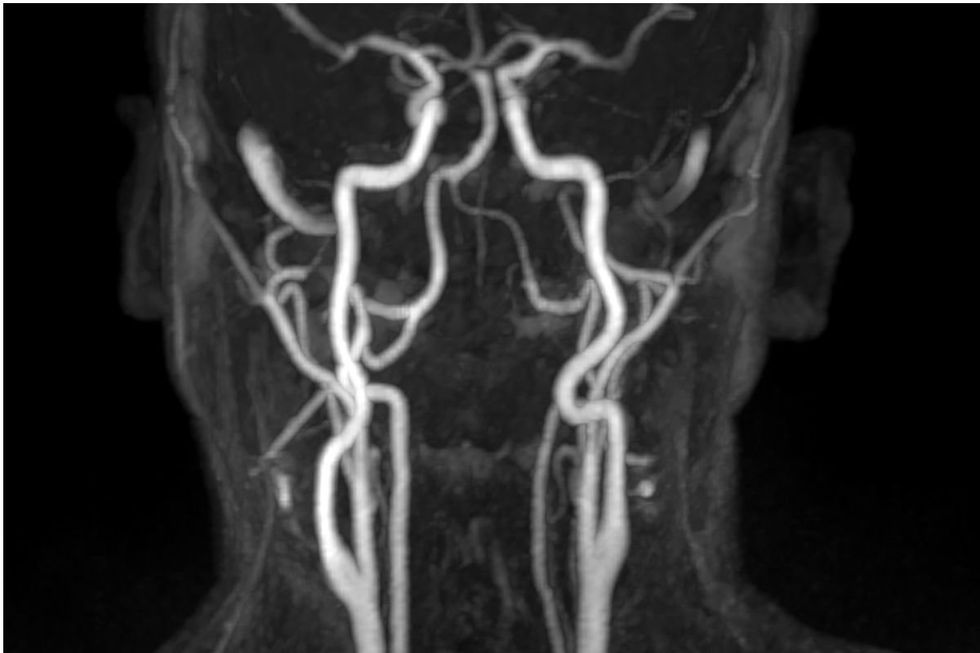

“Níveis mais elevados de cálcio circulante na faixa normal estão associados ao aumento da espessura das principais artérias que levam ao cérebro e a uma maior prevalência de calcificação da aorta abdominal e mais placas calcificadas nas artérias coronárias”, disse ele.